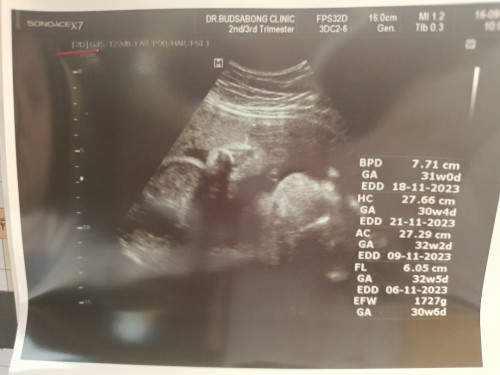

แม่แต่ละคนเป็นไงบ้างคะ น้ำหนักน้องเท่าไหร่กันบ้าง ไตรมาส 3 ใครง่วงนอนบ่อยเหมือนแม่บ้างคะ มาแชร์อาการท้องตอน 33W ได้นะคะ ช่วงนี้น้องโก่งตัวบ่อย ท้องแข็งบ่อย ไปหาหมอมาวันนี้หมอบอกให้นอนเยอะๆ แม่บ้านนี้น้ำตาลความดันปกติดี น้ำหนักลดมา 2 ขีด แต่ต้าวอ้วนแม่ 2,400 กรัมแล้ว แม่จะเดินไม่ไหวแล้ว #ท้องแรก #ลูกสาวคนแรก #ทีมพฤศจิกา66 #ทีมผ่าคลอด